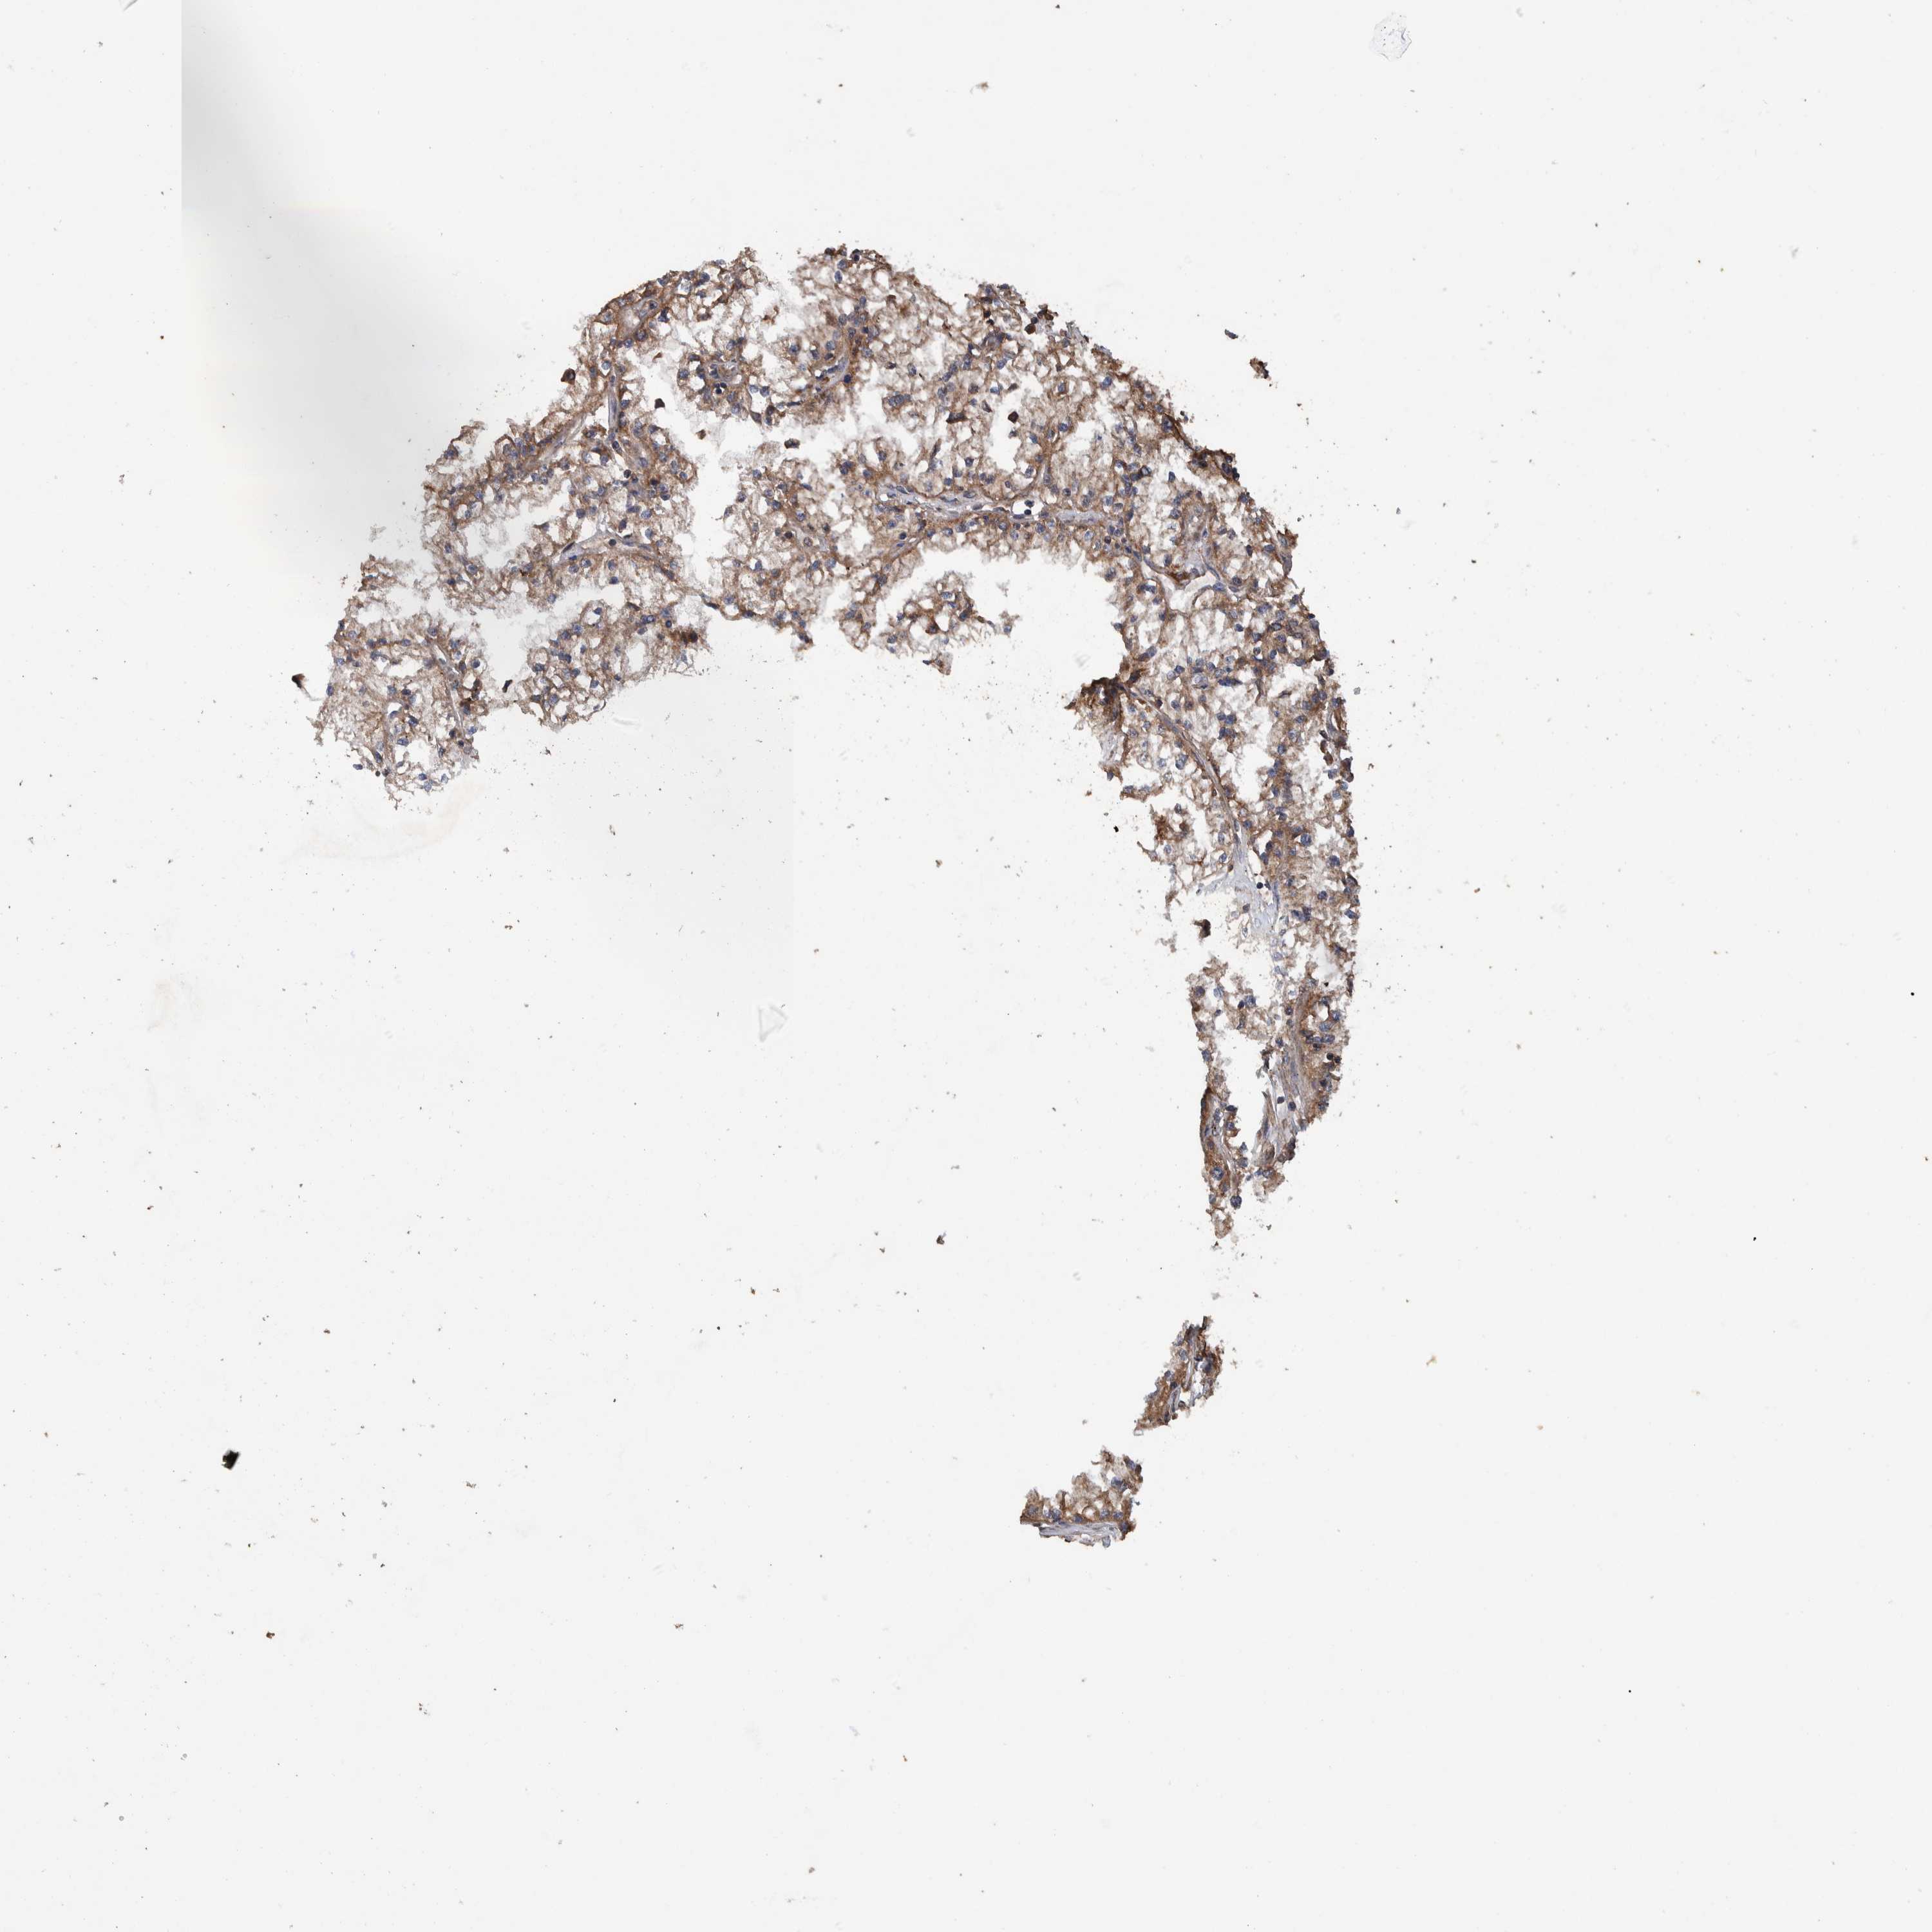

KIDNEY RENAL CLEAR CELL CARCINOMA (VALIDATION) - Interactive survival scatter ploti

The Survival Scatter plot shows the clinical status (i.e. dead or alive) for all individuals in the patient cohort, based on the same data that underlies the corresponding Kaplan-Meier plots. Patients that are alive at last time for follow-up are shown in blue and patients who have died during the study are shown in red.

The x-axis shows the expression levels (FPKM) of the investigated gene in the tumor tissue at the time of diagnosis. The y-axis shows the follow-up time after diagnosis (years). Both axes are complimented with kernel density curves demonstrating the data density over the axes. The top density plot shows the expression levels (FPKM) distribution among dead (red) and alive patients (blue). The right density plot shows the data density of the survived years of dead patients with high and low expression levels respectively, stratified using the cutoff indicated by the vertical dashed line through the Survival Scatter plot. This cutoff is automatically defined based on the FPKM cutoff that minimizes the p-score. The cutoff can be changed by dragging the vertical line or by entering a cutoff value in the square labeled "Current cut-off".

Under the Survival Scatter plot the p-score landscape (black curve; left axis) is shown together with dead median separation (red curve; right axis). Dead median separation is the difference in median mRNA expression between patients who have died with high and low expression, respectively. It is calculated as follows: median FPKM expression of dead patients with high expression - median FPKM expression of dead patients with low expression. This is intended to aid the user in visually exploring custom cutoffs and the associated p-scores and dead median separation.

Individual patient data is displayed and can be filtered by clicking on one or more of the category buttons on the top of the page. Categories describing expression level and patient information include: high, low, alive, dead, female, male and tumor stages. The scale of the x-axis can be toggled between linear and log-scale by clicking on the "x log" button. Mouse-over function shows TCGA ID, patient information and mRNA expression (FPKM) for each patient.

& Survival analysisi

Kaplan-Meier plots summarize results from analysis of correlation between mRNA expression level and patient survival. Patients were divided based on level of expression into one of the two groups "low" (under cut off) or "high" (over cut off). X-axis shows time for survival (years) and y-axis shows the probability of survival, where 1.0 corresponds to 100 percent.

TRIM16 is potential prognostic, high expression is unfavorable in Kidney Renal Clear Cell Carcinoma (validation)

Best expression cut offi

Based on the FPKM value of each gene, patients were classified into two groups and association between prognosis (survival) and gene expression (FPKM) was examined. The best expression cut-off refers the FPKM value that yields maximal difference with regard to survival between the two groups at the lowest log-rank P-value. Best expression cut-off was selected based on survival analysis .

When clicking on this number, the vertical dashed line indicating cut-off, the interactive survival plot, and the Kaplan-Meier curve will be adjusted to show results based on the best expression cut-off.

: 13.11

P scorei

Log-rank P value for Kaplan-Meier plot showing results from analysis of correlation between mRNA expression level and patient survival.

N/A

5-year survival highi

5-year survival for patients with higher expression than the expression cutoff.

For melanoma and glioma, 3-year survival is shown.

5-year survival lowi

5-year survival for patients with lower expression than the expression cutoff.

TCGA RNA samplesi

RNA-seq data is reported as average FPKM (number Fragments Per Kilobase of exon per Million reads), generated by the The Cancer Genome Atlas (TCGA) .

Normal distribution across the dataset is visualized with box plots, shown as median and 25th and 75th percentiles. Points are displayed as outliers if they are above or below 1.5 times the interquartile range. FPKM values of the individual samples are presented next to the box plot.

Average pTPM 11.6

Number of samples 100